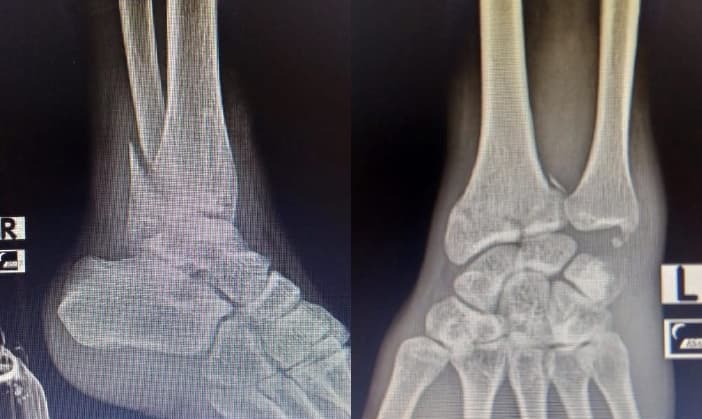

Long story short, I had a motorcycle accident in mid-2021 which resulted in fractures in my right ankle and left wrist.

Recovery took 9 months, during which it was hard to walk and also to type.